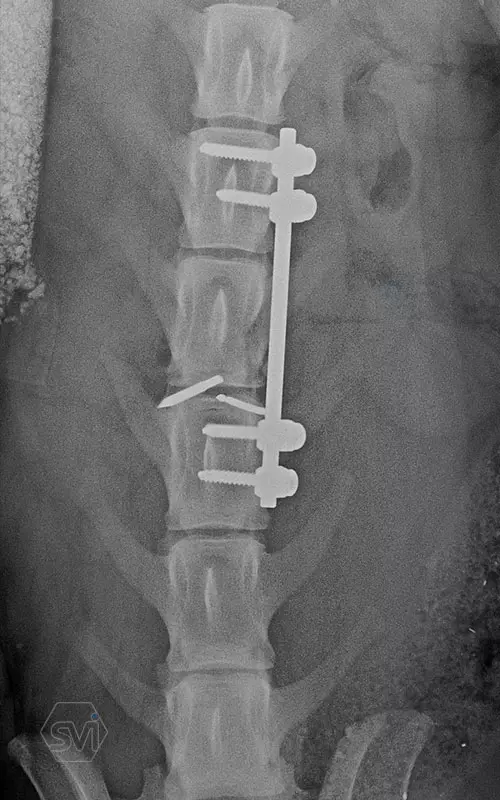

Kutya neve: Benetton, az SOP-LC hatékonysága és stabilitása magáért beszél, a gyógyulás alatt a gerinc folyamatos terhelés alatt volt, és a fémek nem mozdultak el. A kutya szerencsére neurológiailag i felépült! Tehát van esély a gerinctörések esetén is a gyógyulásra...